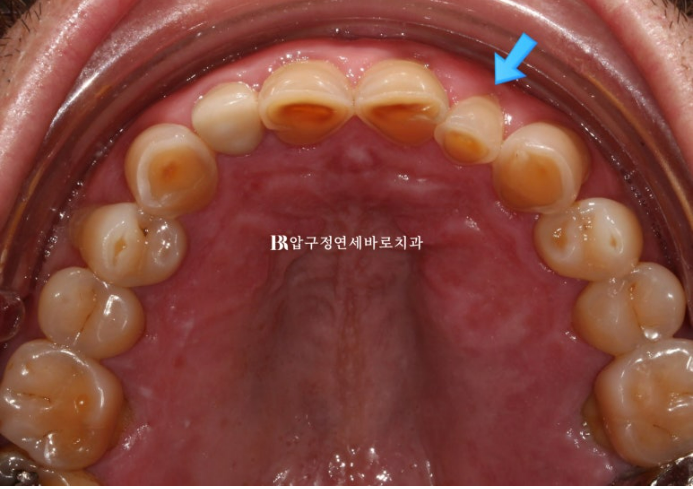

24.03

치아가 오랜 세월 마모로 인하여 짧아진 상태이며, 파란 화살표는 크라운 입니다.

파란 화살표 치아가 뒤로 들어가 있으니 배열을 맞추기 위해서 두껍게 제작이 될 것 입니다.

장기적으로 치아와 잇몸건강을 해치게 되는 거죠

치아가 삐뚤한데 무삭제 라미네이트를 하면 이렇게 됩니다.

이런 치료는 하면 안됩니다.

당장 바둑알 같은 것을 앞니에 달고 있으니,, 불편한 것을 떠나서 장기적으로 구강건강을 해치게 됩니다.

가장 건강한 방법은 단기 앞니 부분교정으로 앞니를 먼저 가지런하게 배열하는 것 임을 설명 드리고 환자분 동의하에 MTA 미니튜브 부분교정 먼저 진행했습니다.